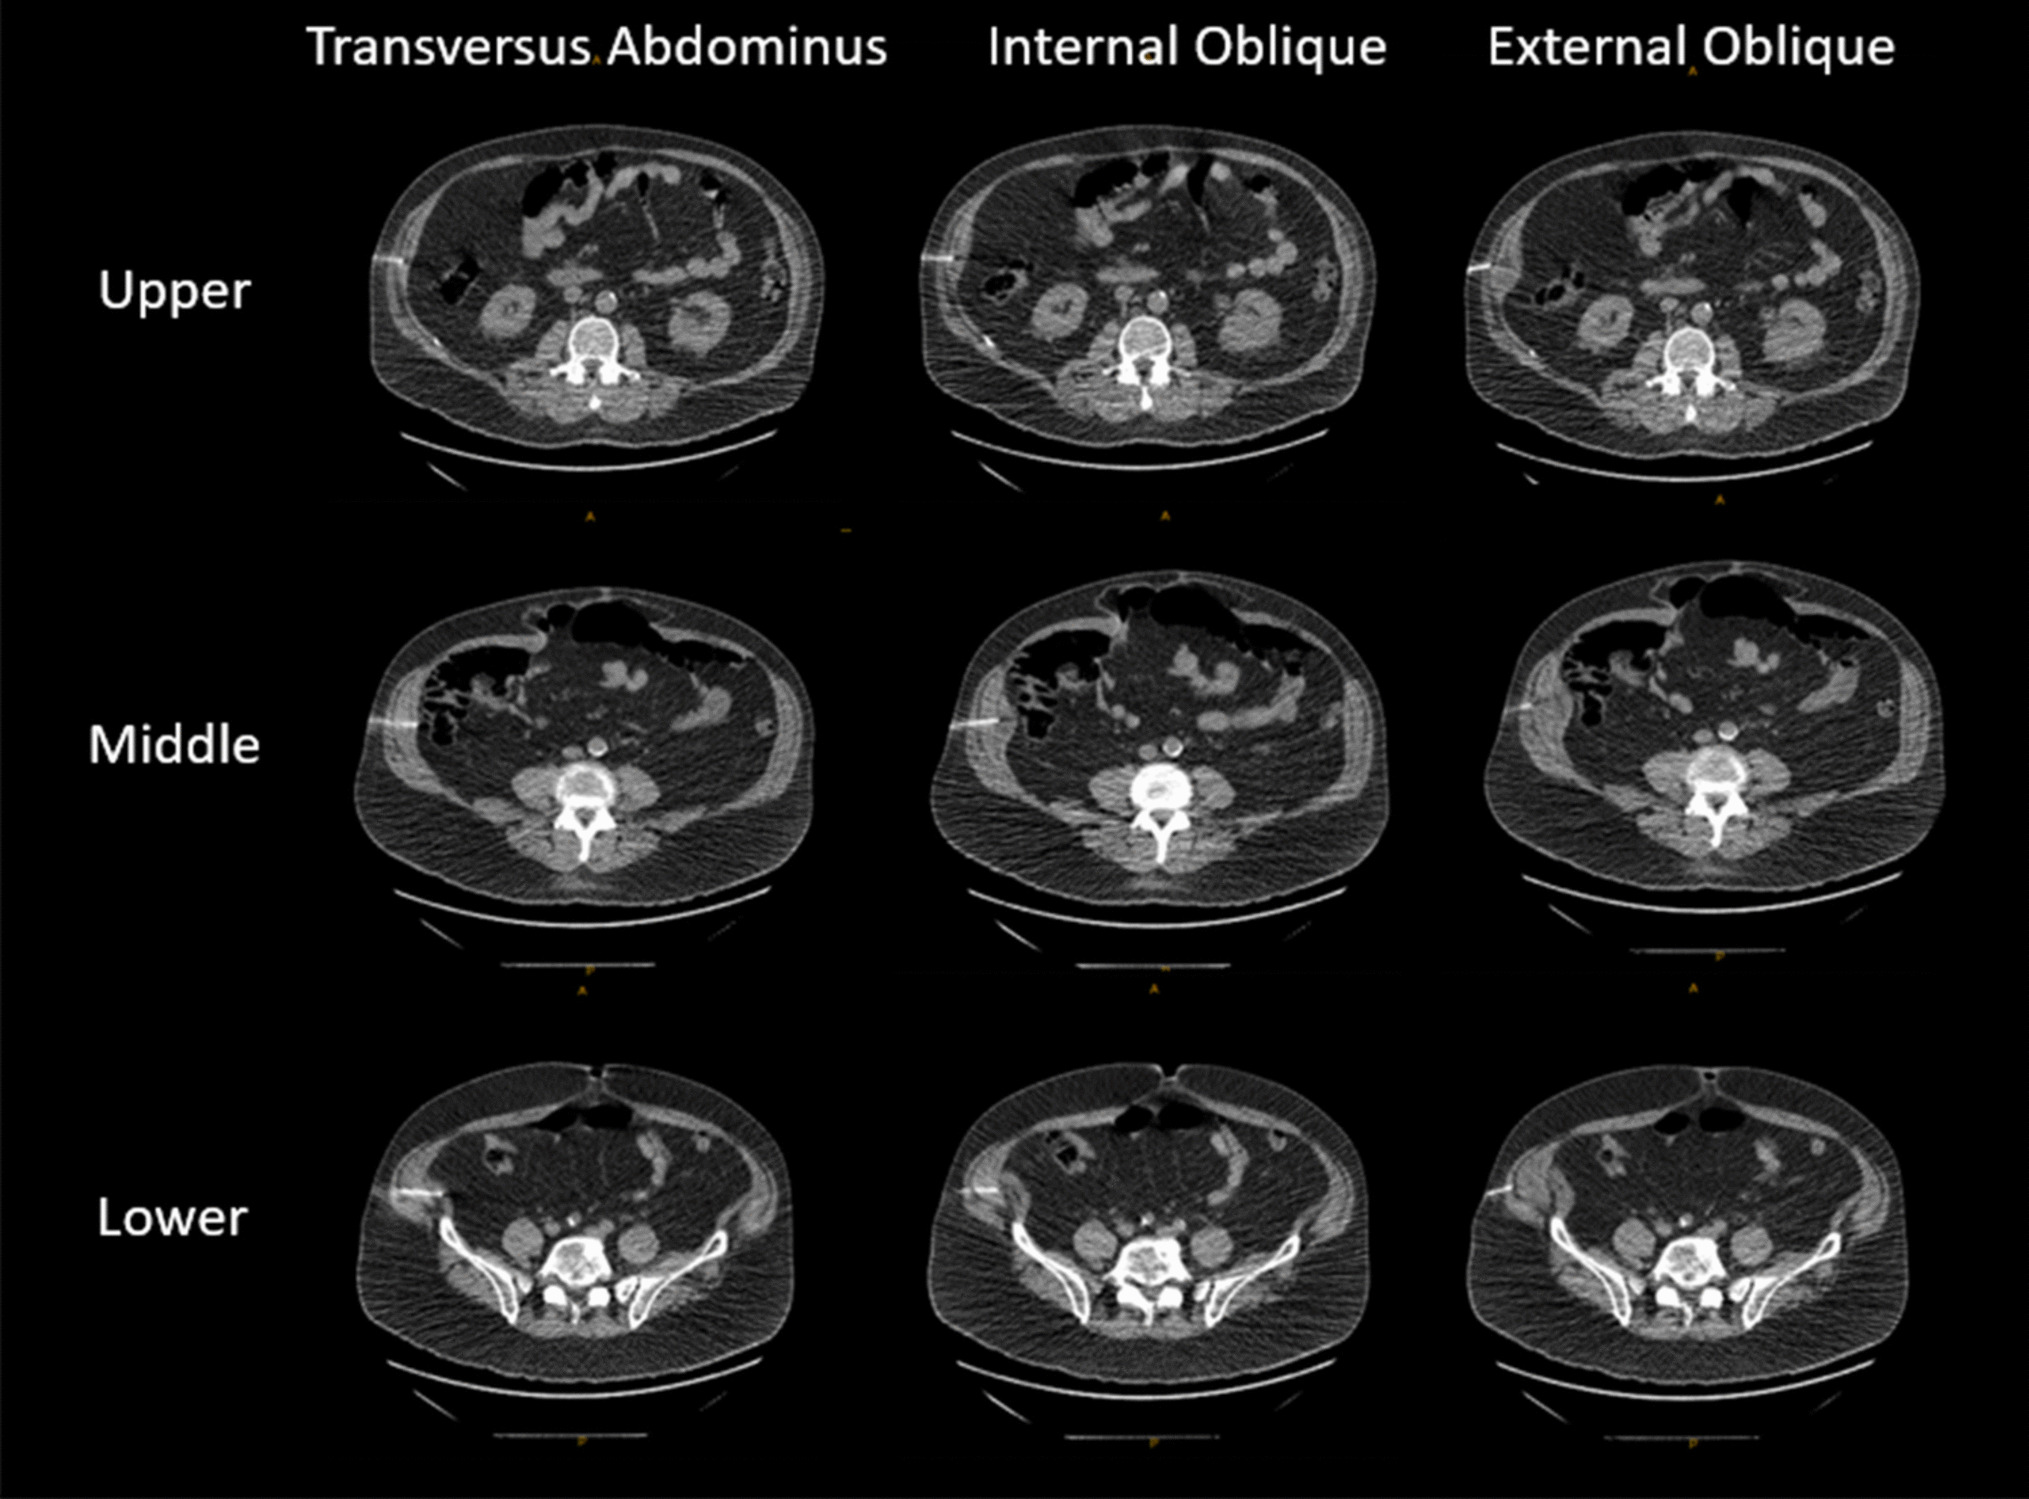

A computed tomography (CT)-guided percutaneous bilateral injection of Botox into the abdominal wall musculature was performed for each patient in the Botox group using the technique described by Zielinski and Zendehas [13, 14]. Briefly, 300 international units of OnabotulinumtoxinA were diluted in 180 ml of sterile normal saline. Six total sites were selected—three on each side along the mid-axillary line: one immediately below the rib cage, one immediately above the iliac crest, and a third midpoint site equidistant between them. The sites were prepped using maximal sterile technique. Moderate sedation was provided with 1–2 mg midazolam and 50 μgr fentanyl with continuous monitoring. Local anesthesia was applied at each site. Under CT fluoroscopic guidance, a 22-guage needle was advanced into each of the external oblique, internal oblique, and transverse abdominis muscles at each site (superior, mid, and inferior bilaterally) (Fig. 2). After confirming negative test aspiration, 10 mL of diluted Botox serotype A was injected into each muscle at each site for a total of 18 injections. Post-injection imaging demonstrated fluid expansion within the muscle layers, confirming appropriate intramuscular delivery.

Fig. 2

Computed tomography (CT)-guided injection of OnabotulinumtoxinA into the abdominal wall muscles, with three injection points (upper, mid, and lower) per muscle, totaling nine injections per side. The injections on the right side are shown here